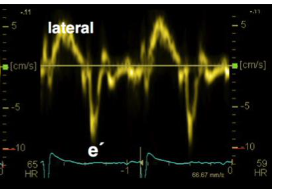

what 2 places do you perform tissue doppler

mitral annulus on the lateral and septal walls

normal lateral E prime velocity

13.3 cm/s